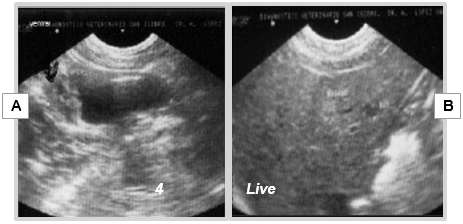

The postoperative period progresses without particular issues, except for slight hematuria lasting 24-48 hours. The patient demonstrates a favorable course of bladder healing (Figure 18A) and early signs of hepatic metastasis at 4 months (Figure 18B).

Figure 18 Ultrasonographic image at 4 months post-cryosurgery.

A) Scar on the dorsal wall of the bladder; B) Hepatic metastasis.